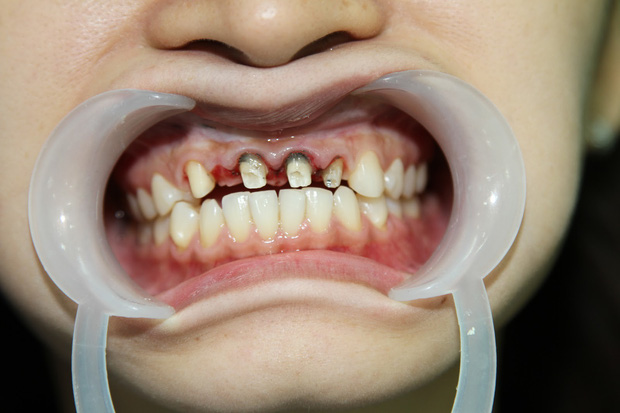

Quy trình thực hiện sai kỹ thuật

Tại các cơ sở nha khoa thiếu uy tín, bác sĩ thường mài răng quá đà để lắp sứ nhanh, dẫn đến hỏng tủy răng. Đối với dịch vụ Implant, việc đặt trụ sai vị trí do thiếu máy móc chẩn đoán hình ảnh (như máy CT Cone Beam) có thể gây tổn thương dây thần kinh hoặc làm trụ bị đào thải chỉ sau vài tháng.